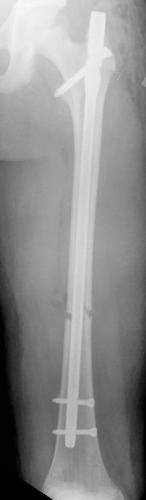

Fracture du fémur – Enclouage centro-médullaire

Chez le grand enfant, la fracture de fémur peut être traitée par un enclouage centro-médullaire qui apporte plus de stabilité à la fracture.

Ce traitement est possible à partir de 11-12 ans chez la fille et 13-14 ans chez le garçon.